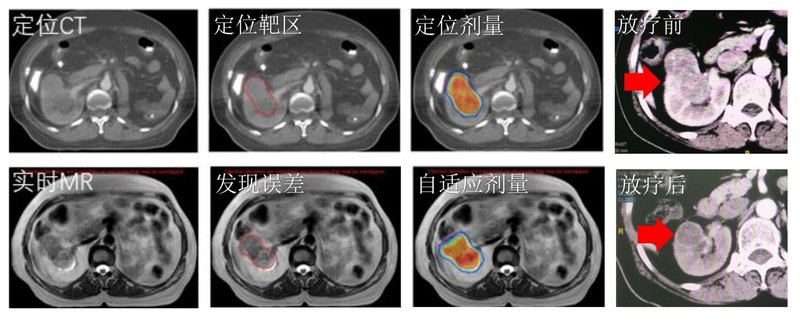

X女士2021年8月突發(fā)腹痛,在當(dāng)?shù)蒯t(yī)院檢查發(fā)現(xiàn)右腎有腫塊。不幸的是,10年前,她曾經(jīng)因?yàn)樽竽I癌做了根治術(shù),目前只有一個(gè)腎,而這僅有的一個(gè)腎卻長了腫瘤,這讓X女士苦惱不已。因?yàn)槟[瘤侵犯了腎門,若手術(shù)切除,將面臨著需要終身透析的結(jié)局;若選擇射頻消融,也難以避免漏尿出血的風(fēng)險(xiǎn)。面對(duì)兩難的抉擇,X女士帶著保腎與根治腫瘤的愿望,來到了中山大學(xué)腫瘤防治中心放療科,找到了何立儒主任醫(yī)師。手術(shù)是早期腎癌患者的主要根治性治療手段,但對(duì)于孤立腎、對(duì)側(cè)腎功能不全、雙腎原發(fā)癌,腫瘤靠近腎蒂、保腎手術(shù)難度大,無法手術(shù)切除、無法耐受手術(shù)或拒絕手術(shù)的患者,立體定向放療可以讓“保腎+根治腫瘤”同時(shí)實(shí)現(xiàn),解決手術(shù)困難的腎癌治療難題。由于X女士僅存的一個(gè)腎也長了腫瘤,有著強(qiáng)烈的保腎需求,且立體定向放療后,腫瘤復(fù)發(fā)率低于5%,對(duì)早期腎癌的治療安全有效。何立儒主任醫(yī)師在國內(nèi)率先開展磁共振引導(dǎo)下腎癌自適應(yīng)立體定向放療技術(shù)。該將診斷級(jí)高場磁共振和先進(jìn)的直線加速器完美結(jié)合,在放射治療的各個(gè)階段(治療前、治療中、治療后)、在線、實(shí)時(shí)的通過磁共振圖像來引導(dǎo)和優(yōu)化放射治療,從而實(shí)現(xiàn)個(gè)體化的精準(zhǔn)放療。X女士選擇了磁共振引導(dǎo)下自適應(yīng)立體定向放療,治療過程順利。放療后一年復(fù)查腫瘤已基本消失,X女士得以停用靶向治療,免于藥物副作用的影響,生活質(zhì)量也得到明顯改善。隨訪至今腫瘤控制良好,腎功能較放療前未見明顯下降。最大限度實(shí)現(xiàn)了保腎的同時(shí)根治腫瘤。X女士和家屬都表示由衷感謝,希望這項(xiàng)技術(shù)能幫助更多病友實(shí)現(xiàn)保腎+根治的愿望。

中山大學(xué)腫瘤防治中心放療科是國內(nèi)最早開展MR引導(dǎo)自適應(yīng)放療的中心之一。自2021年開始用于孤立腎保腎治療以來,已幫助多位患者在保留腎臟同時(shí)獲得了良好的腫瘤控制。下面和大家分享一下該項(xiàng)技術(shù)的特點(diǎn)和優(yōu)勢(shì)。